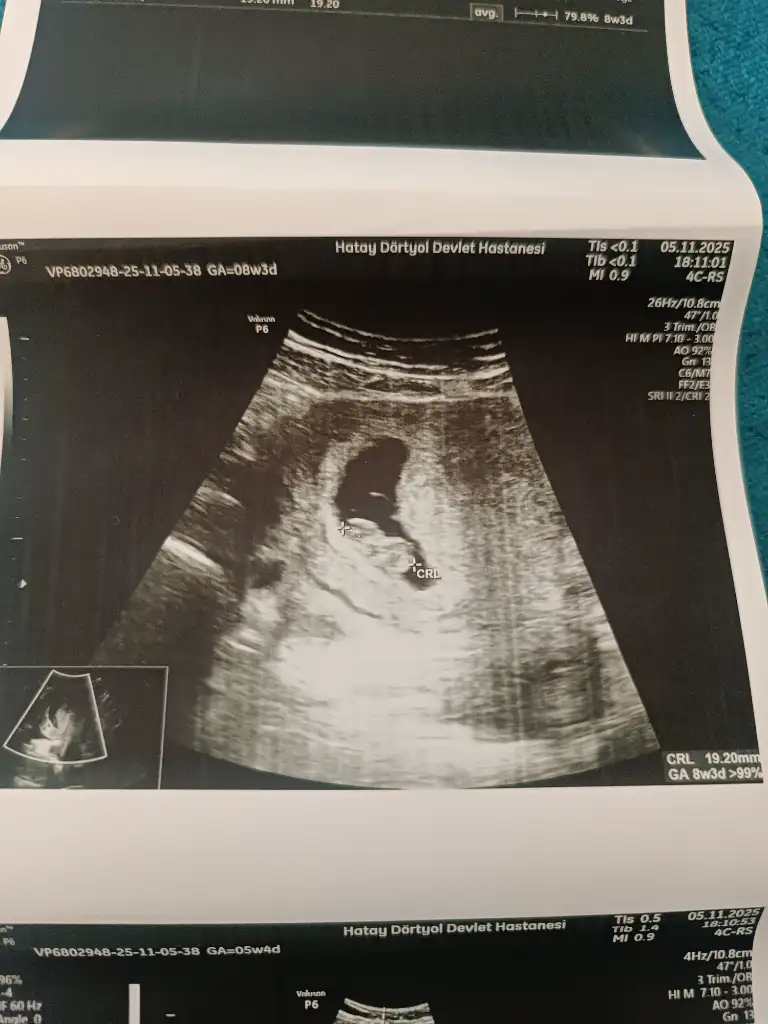

Kizlar hamilelik belirtisi yasamiyordum biliyorsunuz kafamda takılıyordu midemde bulanmiyor sadece midemde gaz sansici vardı bugün doktora gittim doktor 8+3 dedi kalbide çok güzel atıyordu güçlü kalp atışı dedi hiçbir sorun yok haftasıyla uyumlu dedi çok şükür

Cinsiyet belli olurmu kesenin şekline bakarak anlıyorlar ya kizlar yorum yapın bakalım ikinci hamilelik geçiren tecrübeli hamisler😂 8+3 suanki kese

Eklentiler

• IMG_20251105_142205.webp

IMG_20251105_142205.webp

40,7 KB · Görüntüleme: 26